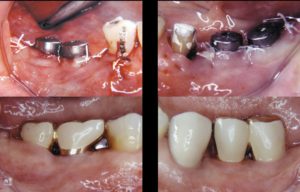

2020.2 治療終了後17年経過 78歳